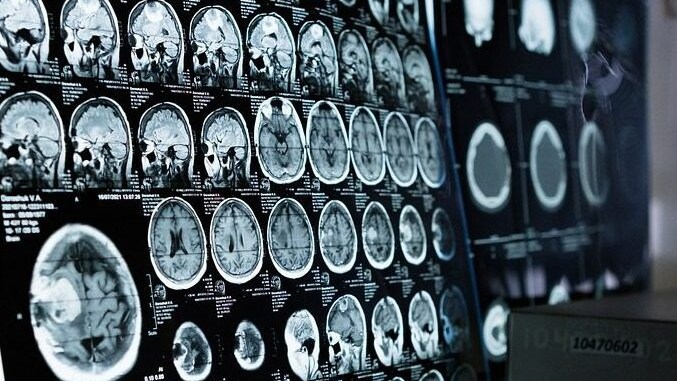

Grosso tumore al cervello asportato dalle sopracciglia, prima mondiale per la tecnica che evita la craniotomia